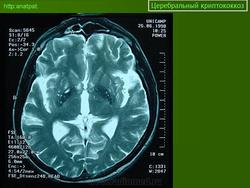

Отдел патологии ТСМ-UNICAMP

Церебральный криптококкоз у ВИЧ инфицированного

Приложения:

150920-9.jpg150920-11.jpg150920-15.jpg150920-21.jpg150920-23.jpg150920-27.jpg150920-33.jpg150920-46.jpg150920-61.jpg150920-79.jpg150920-81.jpg